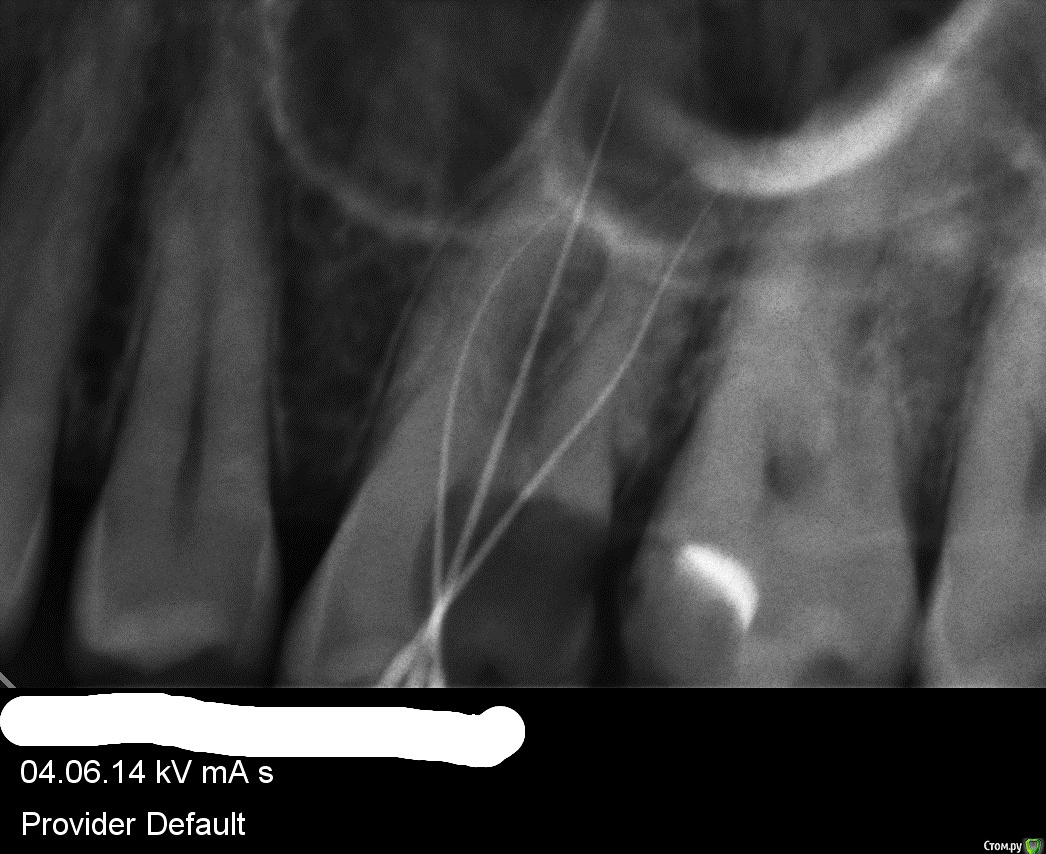

Выкладываю обзорный снимок годичной давности и снимки верхней 6-ки годичной давности, частично там вроде и 7 видно верхнюю левую

post-30402-0-04497700-1431624386_thumb.jpg

post-30402-0-05469600-1431624432_thumb.jpg

Нужен актуальный снимок: возможно, проблема связана с 26 зубом. Если симптоматика будет нарастать, то чисто физически до 24 не дотянете-тогда звоните и записывайтесь с острой болью.

нет сказали что на 27 пломба отошла (глубокий кариес) -см. выше и из-за этого все проблемы - подтекало под пломбу - пульпарная камера рядом что и вызывало болевой синдром и неприятные ощущения.

Не 26 у меня сделан год назад: нервы удалены, каналы пройдены и запломбированы.

да это старые снимки - еще до лечения, вернее во время лечения.

Стоит ли перелечивать 26 зуб если каналы не до конца не запломбированы - чуть чуть верхушки не заполнены , но обработаны полностью

Стоит ли перелечивать каналы если нет никакой симптоматики и не беспокоит этот зуб, так сказать для более лучшего лечения/эффекта ? или лучше не трогать что есть ?